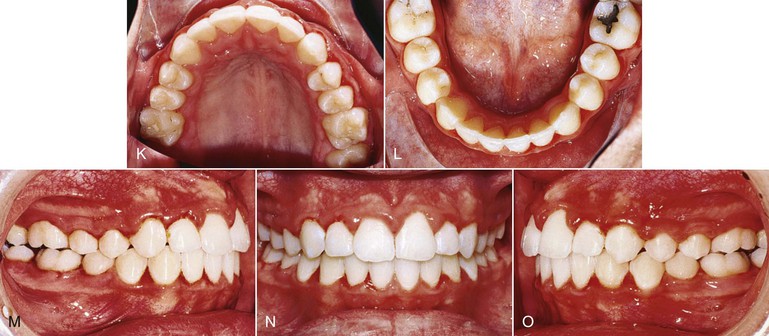

The Jones jig appliance43 is an intraoral noncompliance distalization appliance (Fig. 12-11). It has a modified Nance appliance banded to the second bicuspids, with the Jones jig assemblies tied in place. It consists of a palatal acrylic button of 0.50-inch diameter anchored to the second premolar with a bonded 0.036-inch wire. One arm of the jig fits into a 0.045-inch headgear tube and the second arm fits into a 0.018-inch tube on the first molar. The activation is delivered from the Ni-Ti coil spring tied to the second premolar bracket. The force applied is between 70 and 75 g and average treatment time is 6.35 ± 2.75 months.

Figure 12-11 Jones jig appliance. A, Schematic of the modified Nance appliance banded to the second bicuspids with the Jones jig assemblies tied into place. B–D, Pre-treatment photographs of a patient with a Class II, Division 1 malocclusion, showing the activated appliance. E-G, Intraoral palatal photographs at (from left to right) initial delivery (0 months), 2 months, and 4 months of appliance activation. H–J, Treatment completion. Total treatment time was 24 months. The majority of the time was spent distalizing the premolars, canines, and incisors.

Despite reports of successful correction of Class II malocclusions with the Jones jig, there has been no comprehensive study of molar movement and loss of anchorage during the use of this appliance. To validate its effectiveness, a study was conducted on the patients treated in the office of Dr. Richard Jones, the clinician credited with the design and use of this appliance.44 The sample of 72 patients (26 male and 46 female) was unique. The average age before treatment was 13.8 ± 4.38 years. The results showed molar correction for Class II to Class I malocclusions due primarily to distal movement of the molars. The mean maxillary first molar distal movement was 2.51-mm, with distal tipping of 7.53 degrees. The mean reciprocal mesial movement of the maxillary premolar was 2.0-mm, with mesial tipping of 4.76 degrees. The maxillary first molar extruded 0.14-mm while the maxillary premolar extruded 1.88-mm. The maxillary second molars also moved 2.02-mm and tipped distally 7.89 degrees. Table 12-2 shows the sagittal and vertical movements that accompany the molar distalization procedure with the Jones jig. The changes are highly variable, a factor that should be noted when considering treatment options.